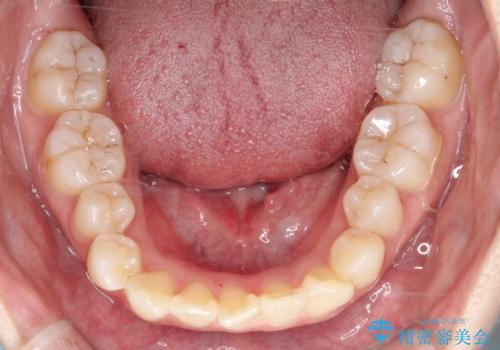

- 患者様は下顎の前歯が3本しかないという特異な歯列を持ち、噛み合わせのバランスが崩れていました。上下の歯の本数が通常と異なるため、抜歯部位の選定が重要となるケースでした。診査の結果、歯の位置や咬合のバランスを考慮し、上顎の両側小臼歯2本と左下の小臼歯1本を抜歯することで、上下の噛み合わせを整える方針としました。矯正装置は、**目立ちにくいハーフリンガル(上顎は裏側矯正・下顎は表側矯正)**を採用しました。

まず、計画通りに抜歯を行い、歯列のスペースを確保しました。上顎は裏側矯正(リンガル)で目立たないように配慮しながら歯を後方へ移動し、下顎は表側矯正を使用して、3本の前歯の位置関係を調整。上下の歯の噛み合わせを細かくコントロールしながら、全体のバランスを整えました。治療後は「歯並びがきれいになり、噛み合わせもしっかり合うようになった」と患者様にも満足していただけました。